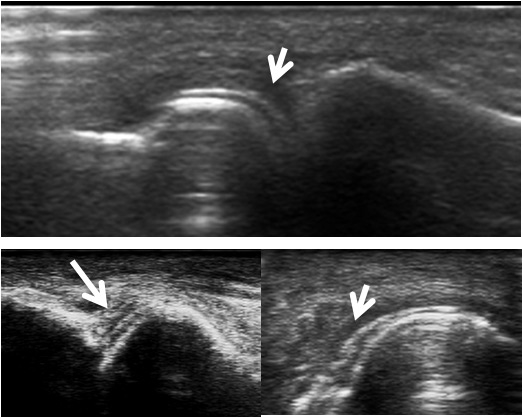

Figure 1

"Double contour" sign in gouty arthritis (white arrows): dorsal view of several metatarso-phalangeal joints performed outside an acute flare of gout.

Some US signs can help to distinguish RA from other causes of arthritis. For example in early psoriatic arthritis (PsA), hypoechoic swelling surrounding the extensor digitorum tendon and peritendinous PD signal seem to predominate compared with intra-articular PD signal in early RA [17]. The described US pattern in PsA seems to confirm the presence of enthesitis [17–18]. US findings such as the presence of a hyperechoic signal within the cartilage layer (calcium pyrophosphate [CPPD] deposition disease) [19] or very superficial cartilage crystals (“double contour” sign in gout) [20] have been described (fig. 1). For CPPD crystal deposition, US imaging can give a positive likelihood ratio (LR) as high as 7.9–29, compared with a much lower positive LR for synovial fluid analysis (7.0) and plain radiography (0.36) [21–22]. Therefore, US has been proposed as an important method for the early diagnosis of CPPD crystal deposition [23]. There are, however, no controlled studies that have examined the capability of US to distinguish morphologically early RA from crystal-associated joint diseases. Osteophytes, one of the morphological hallmarks of osteoarthritis, can also reliably be assessed by US with a good agreement between MRI and US. Of note, US is more sensitive than conventional radiology and clinical examination [2, 4–25]. All of the above-mentioned findings support the idea that US may add important information to the differential diagnosis of articular diseases [26].